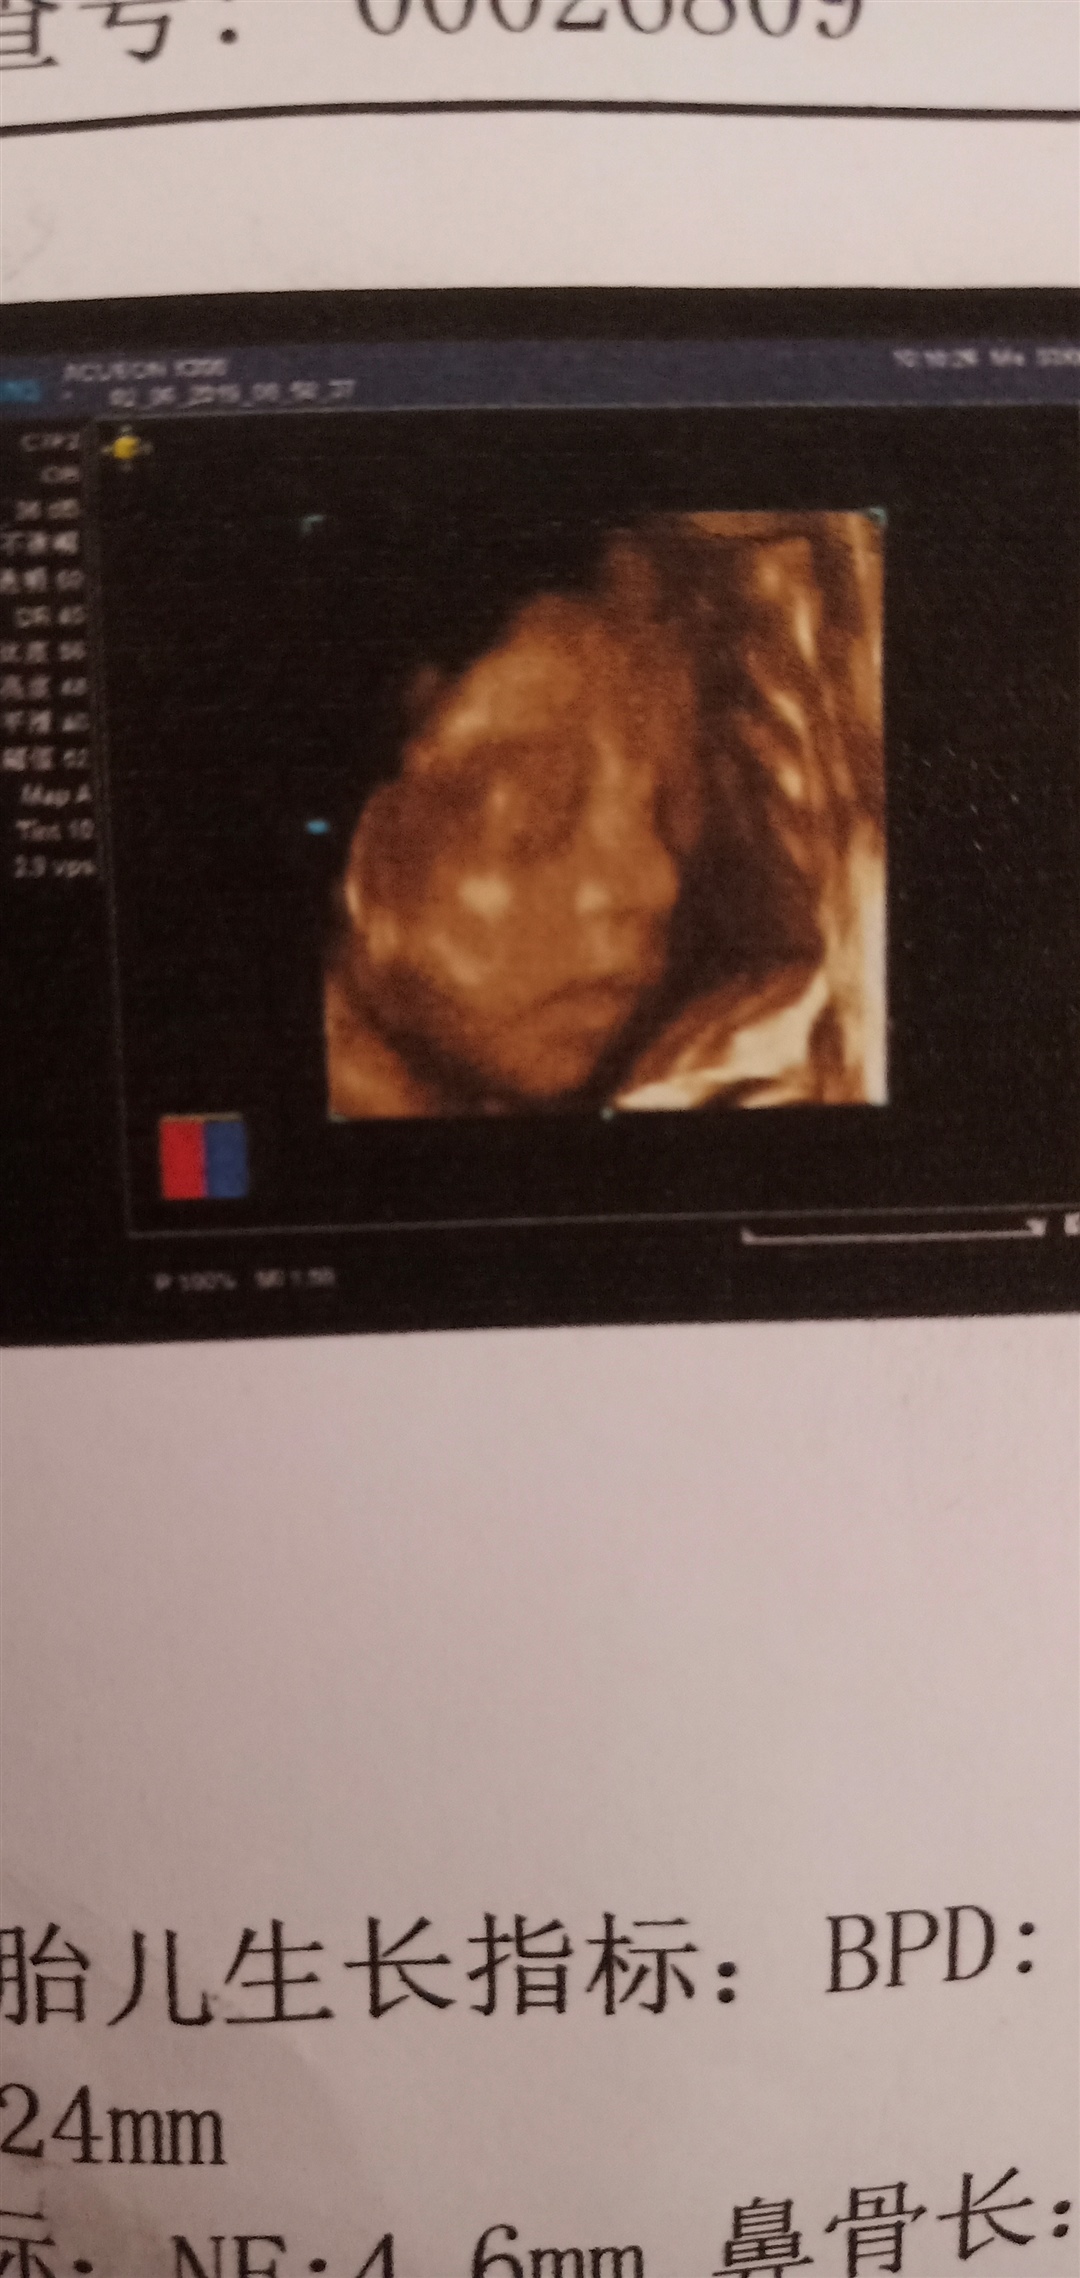

这张怎么看不见